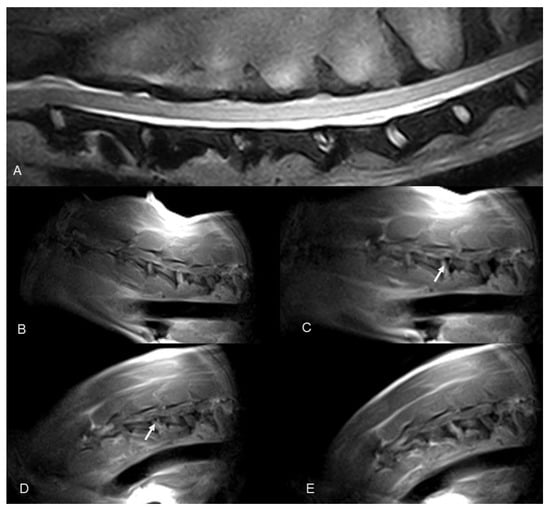

Figure 1. (A) Before, (B) during, and (C) after the ventral slot procedure to remove two intervertebral disks and the dorsal longitudinal ligament.

Figure 3. Dobermann, 8 years old, male entire (Case 7). Cervical spine MRI sample images: (A) T2 weighted mid-sagittal image of the cervical spine. (BE) Real-time kMRI during neck flexion, C4–C5 mild dynamic subluxation is visible (arrows).